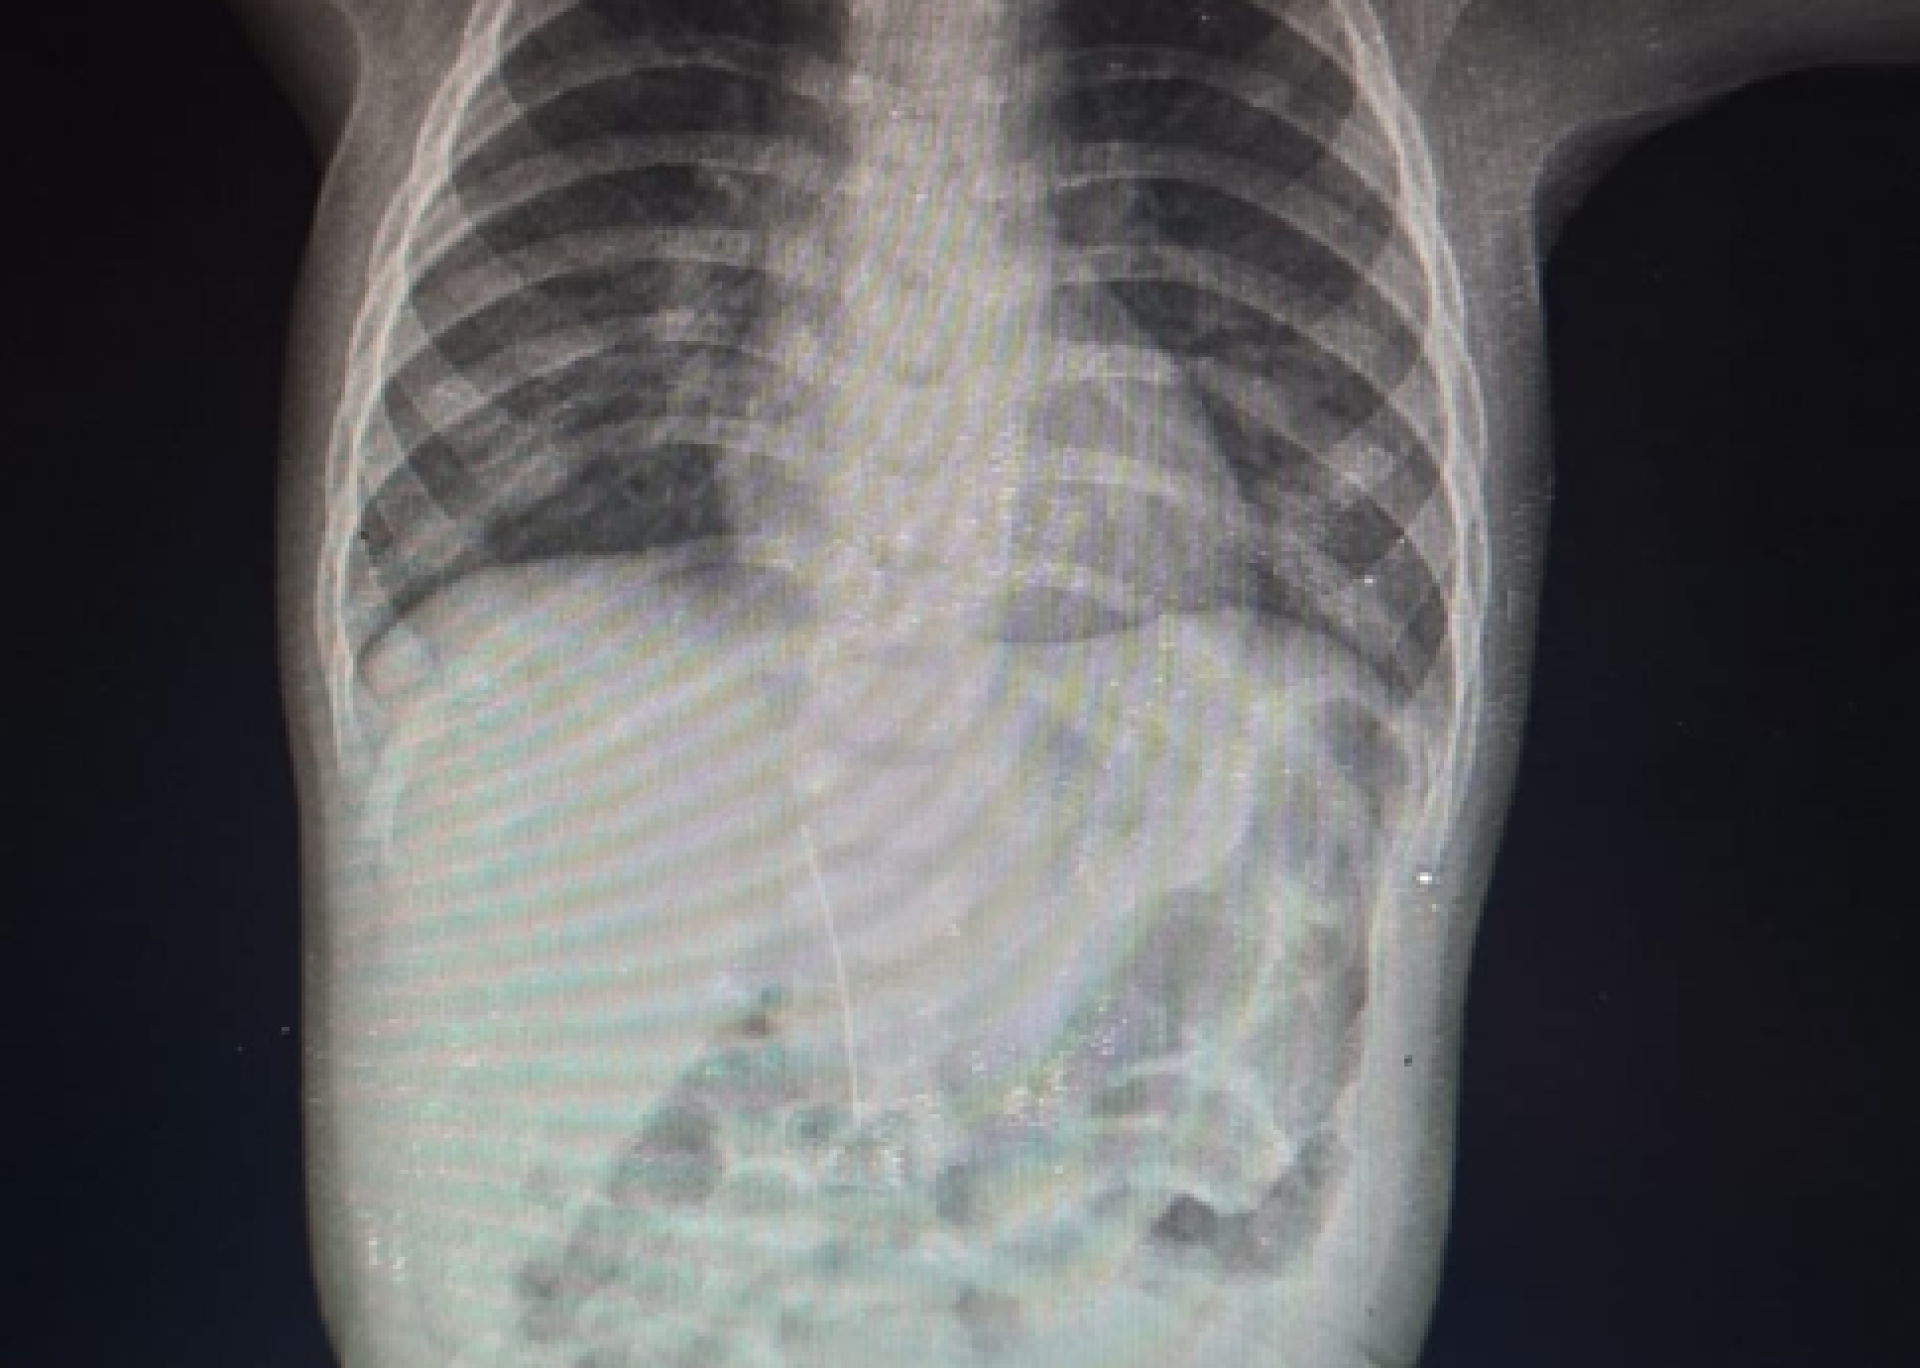

Недавний случай в Туркестане вновь привлёк внимание к вопросам безопасности детей и медицинской помощи. В инфекционное отделение Туркестанской городской центральной больницы был доставлен 8-месячный ребёнок с подозрением на краснуху. Однако, проведённое рентгенологическое исследование выявило неожиданную причину ухудшения состояния малыша.

В ходе обследования врачи обнаружили в брюшной полости ребёнка иглу. Это открытие стало шокирующим, так как беспокойство и повышение температуры тела ребёнка были вызваны не инфекционным заболеванием, а воздействием инородного предмета.

- Игла не попала в организм через пищеварительный тракт.

- Проникновение произошло со стороны печени.

- Мать ребёнка отметила, что малыш не мог самостоятельно проглотить иглу.

Фото предоставлено управлением здравоохранения региона